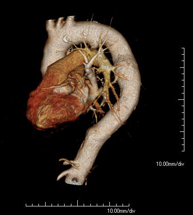

Prova diagnòstica que consisteix en l'estudi de l'aorta toràcica (principal artèria del tòrax) mitjançant l'ús d'un equip de TC (Tomografia Computeritzada). Aquesta tècnica requereix l'ús de contrast iodat i proporciona imatges d'alta definició. L'ús del TCMD (TC multidetector) escurça el temps d'exploració, disminueix la dosi de radiació i millora la qualitat d'imatge. Gràcies als múltiples detectors en determinats estudis es pot acoblar l'obtenció de la imatge amb el batec cardíac, tècnica que permet l'estudi de la vàlvula aòrtica i de l'arrel de l'artèria aorta (primers centímetres) on el batec del cor acostuma a provocar múltiples artefactes de moviment. - Angio –TC Artèries pulmonars (estudi TEP, Tromboembòlia pulmonar)

Diagnostic test to examine the thoracic aorta (main artery of the thorax) using CT (Computed Tomography) equipment. This technique provides high-definition anatomical images. In most cases, the use of iodinated contrast is necessary. The use of MDCT (Multidetector Computed Tomography) shortens scanning time, reduces radiation dose and improves image quality. The multiple detectors used in certain studies enable imaging to be synchronised with the heartbeat, a technique used to study the aortic valve and aortic root (the first few centimetres), where the heartbeat tends to distort images due to movement.